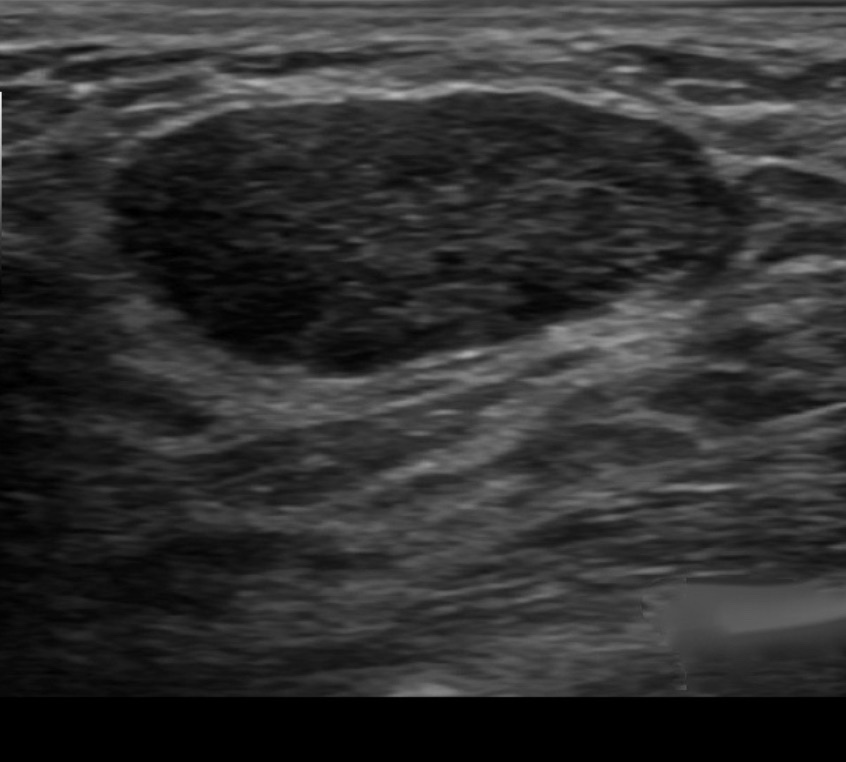

Evaluation of a Breast Mass on Ultrasound

• Elliptical, wider than tall, well-circumscribed and thin echogenic capsule

• Gently lobulated, wider than tall, well-circumscribed and thin echogenic capsule

• Combining the elliptical or gently lobulated shapes with the presence of a complete, thin echogenic capsule:

• Is necessary because many circumscribed carcinomas and most ductal carcinoma in situ are encompassed in a thin, echogenic capsule:

• However, the shape of circumscribed invasive carcinoma or pure ductal carcinoma in situ is rarely elliptical or gently lobulated

• BIRADS 3:

• A 6-month follow-up ultrasound would be appropriate unless the anxiety of the patient makes core biopsy a better option